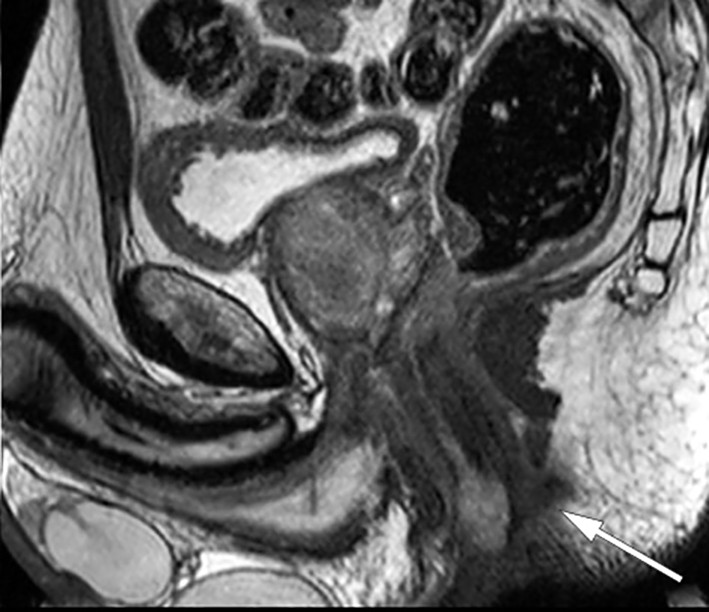

Videre utredning viste normale orienterende blodprøver, inklusive CEA på 1,3 mcg/L (˂ 5,0). To dager etter første kontakt ble pasienten koloskopert med normale funn, foruten de kjente forandringene i nedre analkanal. Histologiske svar på biopsier forelå etter en uke. Biopsier fra rektum viste rektumslimhinne med intestinal spiroketose uten tegn til malignitet. Biopsier fra perianal tumor viste kronisk aktiv plasmacellerik inflammasjon uten tegn til malignitet. Etter ti dager ble det utført MR bekken som viste en malignitetssuspekt tumor på 1,6 × 0,7 × 3,5 cm kl. 12–3 i nedre del av analkanalen med mulig affeksjon av intern analsfinkter (figur 1). I tillegg ble det påvist flere forstørrede lymfeknuter langs arteria og vena iliaca communis på venstre side, i mesorektum og i venstre lyske (figur 2). Den største lymfeknuten i venstre lyske ble målt til 2,0 × 5,4 cm. CT thorax/abdomen/bekken viste forstørrede lymfeknuter langs arteria og vena iliaca communis på venstre side og paraaortalt, men ingen andre tegn til metastaser.

Inflammasjon i rektum kan føre til fortykkelse av tarmveggen som kan gi et tumoraktig utseende, og kan være ledsaget av uttalt lymfadenopati (8). Det er publisert flere kasuistikker hvor lymphogranuloma venereum ble tolket som malign tilstand. Radiologisk kan det være svært vanskelig å skille mellom lymphogranuloma venereum og malignitet som adenocarcinom, lymfom, og lymfeknutemetastaser. Noen ganger kan symptomer og endoskopiske funn ligne på inflammatorisk tarmsykdom (13). Differensialdiagnoser inkluderer derfor infeksiøse, inflammatoriske, iskemiske og neoplastiske prosesser (8, 13).